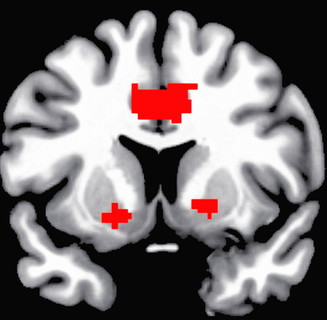

與「血小板」功能有關的基因突變,會提高中風及心臟病發作的機率。英國倫敦大學國王學院團隊日前發表於《公共科學圖書館》線上期刊的研究指出,1組與血小板凝血功能有關的基因「PIA2」若發生突變,會導致血栓較易形...